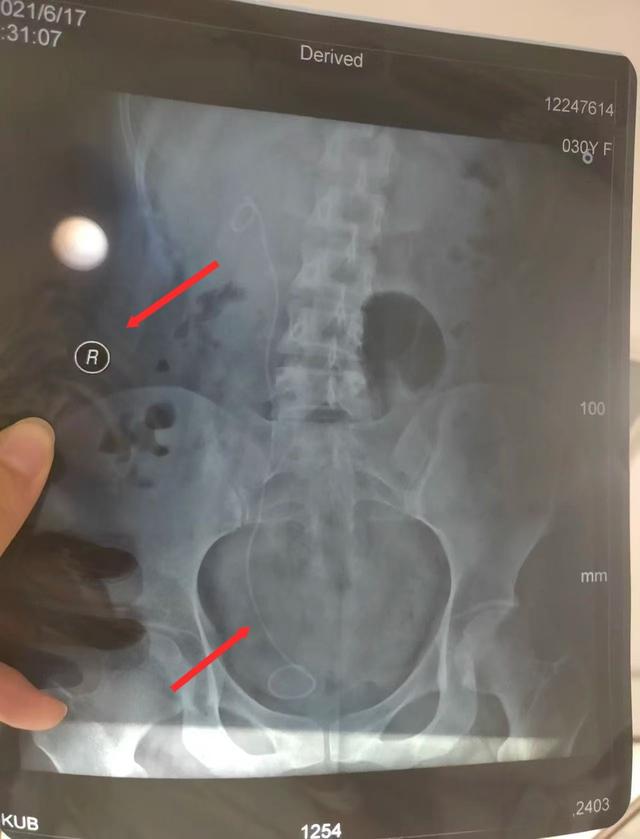

朱女士发现左侧输尿管手术误做在了右侧

“医生为我确定了左输尿管手术方案,包括术前谈话以及手术知情同意书上,主刀医生也都是这位医生。2021年4月21日下午手术顺利进行,不久后出院。”朱女士说,直到术后两个月,她到医院复查拍CT后才发现,自己原本健康的右输尿管内被施行了手术,患病的左输尿管反而没有手术。

鉴定报告认定,华山医院虽然诊断正确,但手术方案有误,存在告知缺陷。2021年4月19日,医方手术知情同意书拟定手术为“左侧输尿管镜狭窄伴左肾积水”,4月21日,术中医方自行变更手术方案且依据不足(患者既往各项检查如超声、CTU、MR均提示泌尿系病变在左侧,术后超声检查亦显示病变在左侧),术中未向患方进行告知并取得患方知情同意,术后亦未告知患方该情况,患方至6月17日门诊复查时知晓该情况。医方告知存在缺陷,在一定程度上延误了患者左侧输尿管病变第二次治疗,时间约2个月。